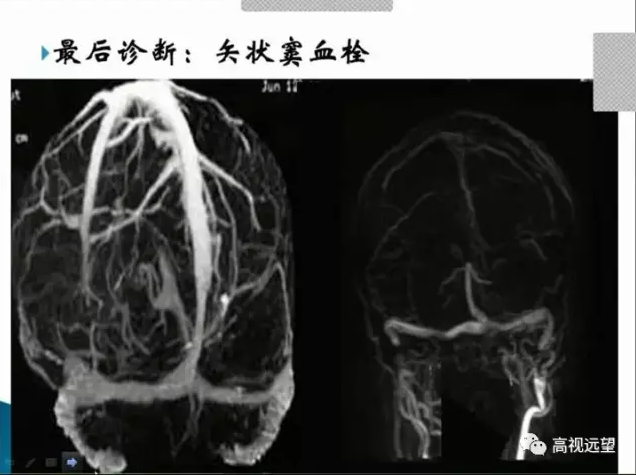

最后诊断:矢状窦血栓

由于眼科医生对颅内静脉窦血栓

疾病(CVST)认识不够,对影像学

检查应用不够,故临床上对此类

疾病较难作出正确诊断。

最佳治疗时机。不过随着眼科医

生认识的提高和影像技术的发展

,特别是MRI和MRV,大大提高

了该病的诊断率。